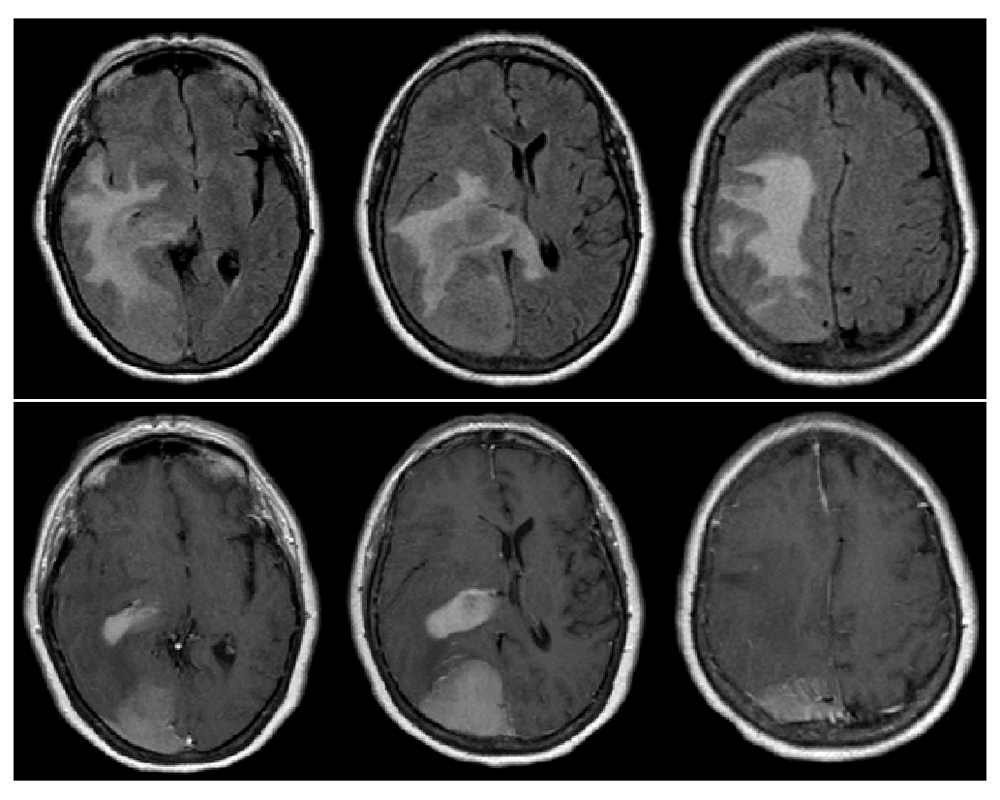

The patient was started on dexamethasone 6mg every 6 hours and admitted to the ICU. A STAT MRI brain with and without contrast revealed two homogeneously contrast-enhancing lesions: a 4.8.×6.1×3cm right parieto-occipital extra-axial mass with dural-based attachment, as well as a 3.4×1.8×2.2cm homogenously contrast-enhancing lesion adjacent to the right posterolateral ventricle. FLAIR signal changes were also appreciated and were noted to extend across the splenium of the corpus callosum, raising concerns for a high-grade glial process (Figure 2).

T1-post contrast reveals 2 distinct lesions – a homogenously enhancing extra-axial lesion in the right parietal lobe as well as a homogeneously enhancing periventricular lesion (bottom).